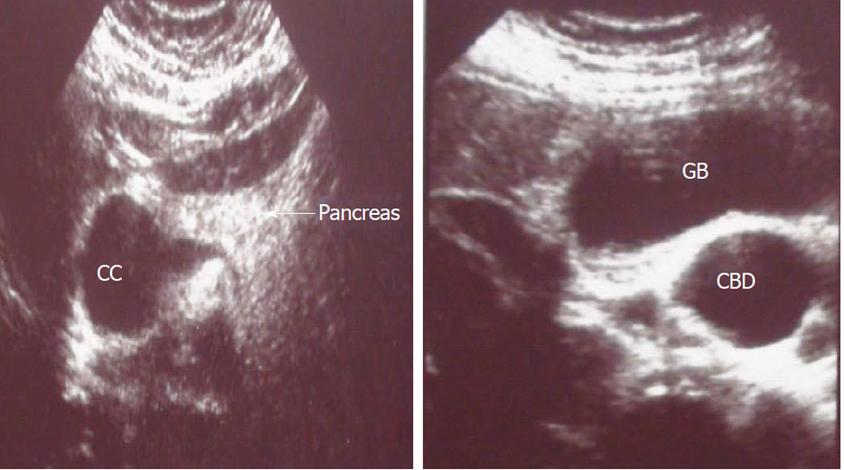

除了典型的腹痛、发热、黄疸、腹部包块等症状之外,胆总管囊肿的诊断还是要依靠影像学检查,其中超声检查可以发现:1)肝门部门静脉前方见边界清楚的囊性包块,多呈球形、张力高,椭圆形,或纺锤形,近端及远端与胆总管相通;2)无继发感染时,囊肿壁为光滑强回声线,较薄,囊内液体清亮,可见胆泥沉积,呈均匀等回声,合并结石时,囊肿内可见高回声团,并伴有声影,改变体位可移动;3)合并感染时,囊肿内可见密集点状回声,当胆总管囊肿破裂穿孔时,可见肝门区及周围粘连及包裹性积液,有时可见包裹积液区与胆总管破损处相通。

超声下胆总管囊肿表现,CC胆总管囊肿,GB胆囊,CBD胆总管,pancreas胰腺